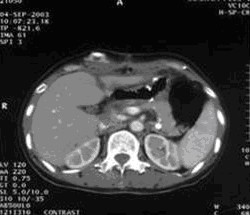

女,49歲。胃體癌晚期,胃竇增厚強(qiáng)化,與周?chē)尺B,腹膜增厚,腹腔廣泛轉(zhuǎn)移,伴大量腹水。放/化療失敗,無(wú)法手術(shù)。治療方案:腹腔灌注今又生2×1012VP/2次/周,共12周,同時(shí)灌注順鉑和5-氟尿嘧啶腹腔,后4周加8次全腹熱療。治療后:第3周,腹水消失;第8周,胃竇、腹膜和網(wǎng)膜變薄,盆腔結(jié)節(jié)明顯變小。后行手術(shù)切除殘余胃腫瘤,術(shù)中探查全腹和盆腔未捫及腫瘤。術(shù)后病檢胃腫瘤內(nèi)未見(jiàn)癌細(xì)胞。

治療結(jié)束:第12周,胃壁回復(fù)正常

殘胃